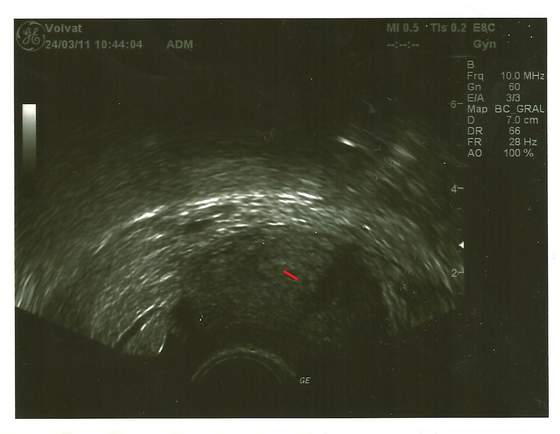

Wracam właśnie od ginki. :-):-):-) Wszystko jest w porządku, Groszek jest bardzo malutki, ale mam go na zdjęciu!!!

A oto mój Groszek - jeszcze bardzo maleńki i naprawdę ledwo widać, ale jest! :-):-):-)

Zobacz załącznik 339174